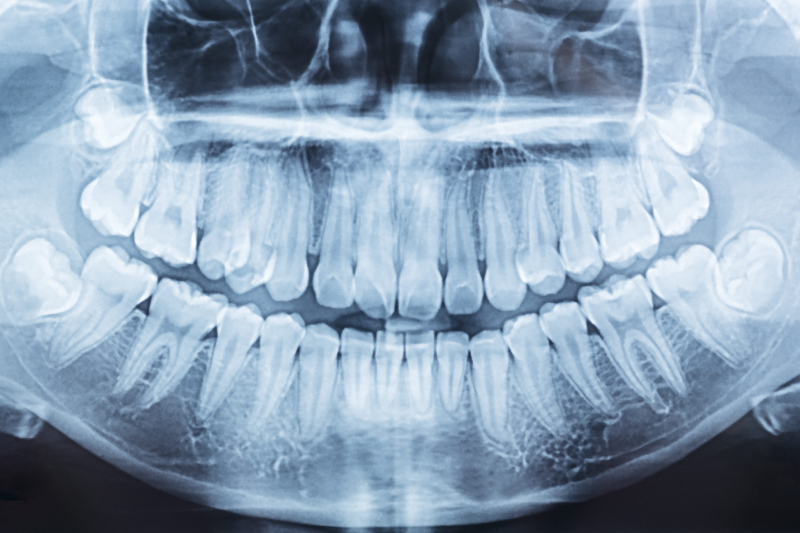

Wykonujemy diagnostykę RTG zębów i szczęk, dzięki której lekarz może szybko ocenić sytuację i dobrać plan leczenia.

Panoramiczny obraz przeglądowy całego uzębienia, szczęki i żuchwy. To badanie jest fundamentem profilaktyki – pozwala wykryć zatrzymane ósemki, zmiany okołowierzchołkowe czy torbiele, które nie dają objawów bólowych. Wykonujemy je zgodnie z normami ustawy Prawo Atomowe, dbając o pełną ochronę radiologiczną.

Pantomograficzny rentgen zębów OPG może być zalecany pacjentom, którzy trafiają do gabinetu stomatologicznego po raz pierwszy lub po dłuższej przerwie. Pełna diagnostyka cyfrowa w odróżnieniu od zdjęcia punktowego pozwala na uzyskanie obrazu odzwierciedlającego stan zdrowia pacjenta w obrębie całego uzębienia. Pozwala także na zaobserwowanie, czy występują takie nieprawidłowości jak torbiele zmiany próchnicze, ubytki, torbiele, zęby zatrzymane czy stany patologiczne kości.

W klinice stomatologicznej SmileUp dysponujemy własnym centrum diagnostycznym. Dzięki temu możemy uzyskać natychmiastową ocenę uzębienia przy bardzo małej dawce promieniowania. Najczęściej w naszym gabinecie przeprowadzamy badanie pantomograficzne RTG zębów . Wykonanie zdjęcia rentgenowskiego jest przydatne między innymi przy planowaniu leczenia kanałowego, ocenie stanów zapalnych i zmian próchniczych, a także przy analizie wypełnień i implantów.